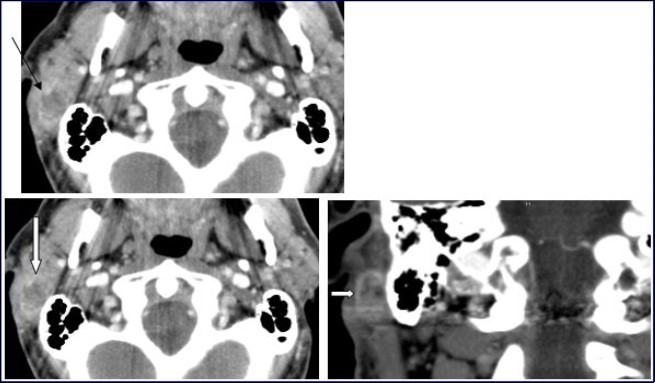

A 54-year-old man consulted for right retro-auricular mass, painless but pruritic, lasting for two months and growing fast. No significant findings in the medical or surgical history. Physical examination revealed a right retro-auricular mass, fixed to the underlying soft tissues measuring 4 x 3 x 3 cm3. The mass had a fluctuating center and there were signs of inflammation around it. Head and neck examination didn’t show any abnormalities or lymphadenopathy. Oto-Rhino-Lyryngologycal and whole-body examinations were unremarkable. Laboratory studies resulted within normal limits. A short course of antibiotic therapy was initially given without any results. Fine needle aspiration (FNA) cytology revealed parotid malignant tumor without precision. The chest-X ray was normal. Head and neck CT with intravenous contrast material showed a focal lesion in the right parotid gland with size 3 × 2 cm2, well-defined, heterogeneous with peripheral contrast enhancement and necrotic center. No evidence of pathologic lymph nodes in or around parotid gland or bony involvement (Figure 1) was found.

Figure 1.Computed Tomography of the neck with intravenous contrast material revealed a focal lesion in the right parotid gland with size 3 × 2-cm. The mass was well defined, heterogeneous, with peripheral contrast enhancement (large white arrow). It had a central attenuation value of 13 HU, suggesting a necrotic mass without bony involvement (thin black arrow).